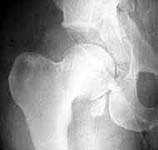

Seeking advice on management of 50 years old male who presented with infected fracture dislocation right hip with complete sciatic nerve palsy three months after injury. Xrays initial and current and CT scan Current images attached.

AP now